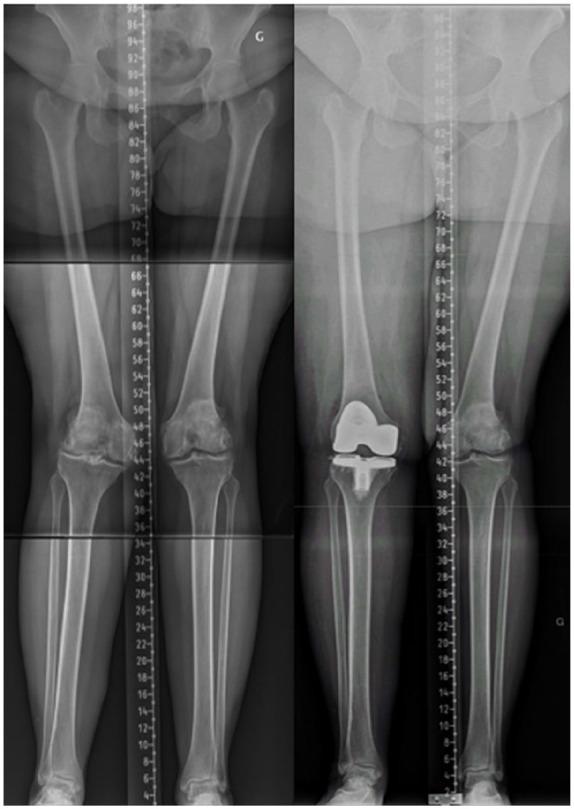

采用运动学对线技术植入全膝关节置换术(TKA)的具体病例考量。

Specific case consideration for implanting TKA with the Kinematic Alignment technique.

The Kinematic Alignment (KA) technique for total knee arthroplasty (TKA) is an alternative surgical technique aiming to resurface knee articular surfaces.The restricted KA (rKA) technique for TKA applies boundaries to the KA technique in order to avoid reproducing extreme constitutional limb/knee anatomies.The vast majority of TKA cases are straightforward and can be performed with KA in a standard (unrestricted) fashion.There are some specific situations where performing KA TKA may be more challenging (complex KA TKA cases) and surgical technique adaptations should be included.To secure good clinical outcomes, complex KA TKA cases must be preoperatively recognized, and planned accordingly.The proposed classification system describes six specific issues that must be considered when aiming for a KA TKA implantation.Specific recommendations for each situation type should improve the reliability of the prosthetic implantation to the benefit of the patient.The proposed classification system could contribute to the adoption of a common language within our orthopaedic community that would ease inter-surgeon communication and could benefit the teaching of the KA technique. This proposed classification system is not exhaustive and will certainly be improved over time. Cite this article: 2021;6:881-891. DOI: 10.1302/2058-5241.6.210042.

全膝关节置换术(TKA)的运动学对线(KA)技术是一种旨在对膝关节关节面进行表面置换的替代手术技术。TKA的受限KA(rKA)技术对KA技术应用了边界条件,以避免重现极端的肢体/膝关节解剖结构。绝大多数TKA病例较为简单,可以采用标准(非受限)方式的KA技术进行手术。在一些特定情况下,实施KA TKA可能更具挑战性(复杂KA TKA病例),应包括手术技术的调整。为确保良好的临床效果,复杂KA TKA病例必须在术前识别并进行相应规划。所提出的分类系统描述了在进行KA TKA植入时必须考虑的六个具体问题。针对每种情况类型的具体建议应提高假体植入的可靠性,从而使患者受益。所提出的分类系统有助于在我们的骨科领域采用一种通用语言,这将便于外科医生之间的交流,并可能有益于KA技术的教学。这个提出的分类系统并不详尽,肯定会随着时间的推移而改进。引用本文:2021;6:881 - 891。DOI:10.1302/2058 - 5241.6.210042。